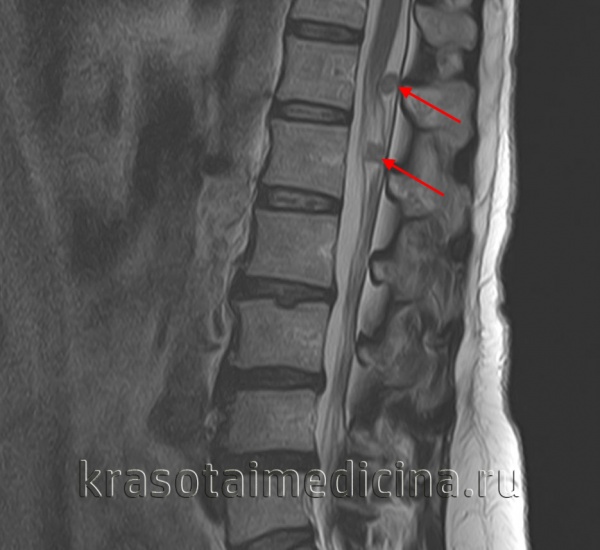

(б) При МРТ на совмещенных Т1 (вверху) и Т2 (внизу) взвешенных изображениях визуализируется овоидноеобъемное образование гомогенной структуры, гипоинтенсивное на Т1ВИ и гиперинтенсивное на Т2ВИ.

Биопсия под контролем КТ позволила подтвердить диагноз шванномы.